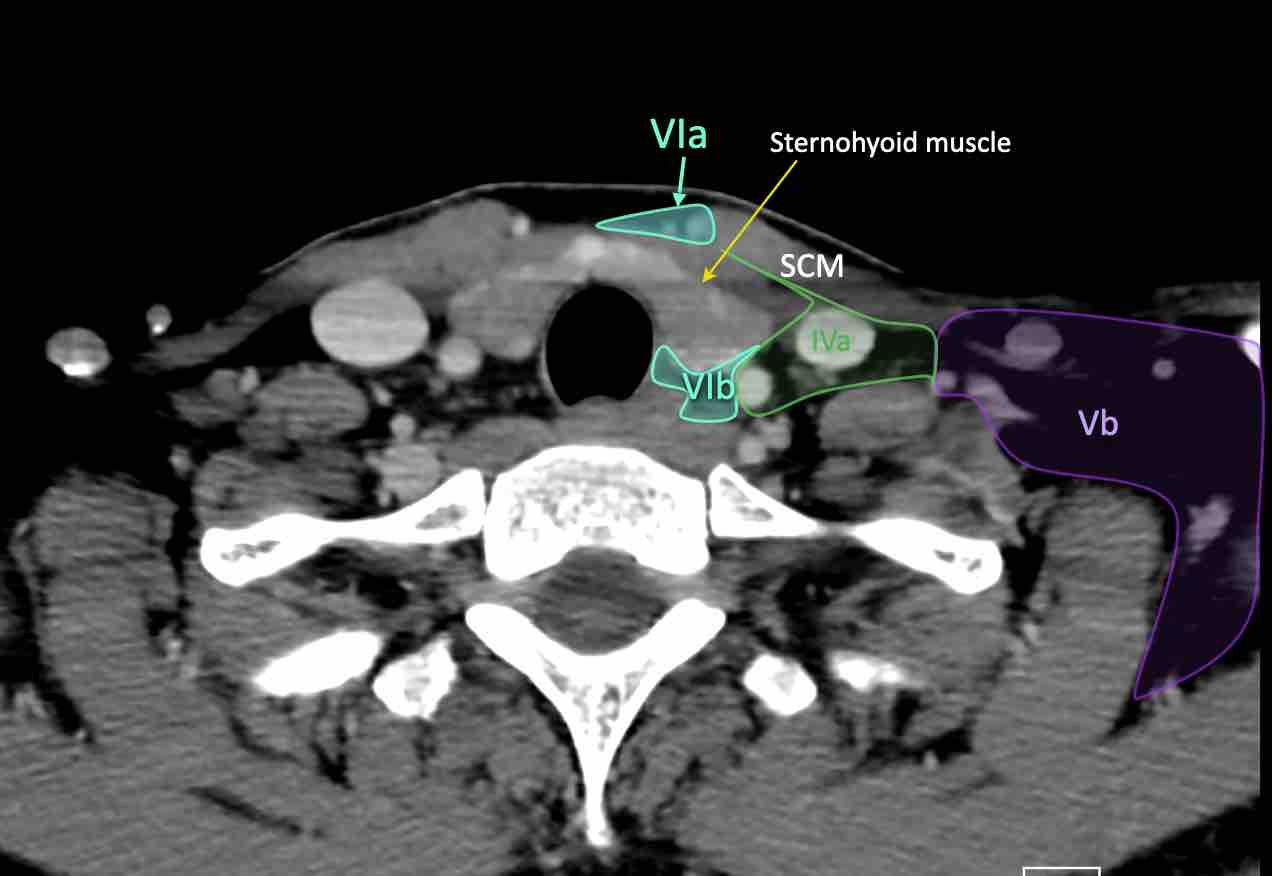

IV – Tĩnh mạch cảnh dưới và hố thượng đòn trong

Ranh giới giữa tầng IVa và IVb được xác định tùy ý tại vị trí 2 cm phía trên khớp ức đòn.

V – Tam giác cổ sau và hố thượng đòn

Tầng V chứa các hạch của nhóm tam giác cổ sau nằm ở phía sau cơ ức đòn chũm, xung quanh phần dưới của thần kinh phụ gai sống và các mạch máu cổ ngang.

Tầng Vc – Hố thượng đòn

Tầng này chứa các hạch thượng đòn bên nằm trong phần tiếp nối của các hạch tam giác cổ sau (tầng Va và Vb) từ các mạch máu cổ ngang xuống đến giới hạn được xác định tùy ý tại vị trí 2 cm phía trên cán ức.

VI – Cổ trước

Tầng này chứa các hạch tĩnh mạch cảnh trước nông (tầng VIa) và các hạch sâu hơn bao gồm hạch trước thanh quản, trước khí quản, cạnh khí quản và hạch thần kinh thanh quản quặt ngược (tầng VIb).